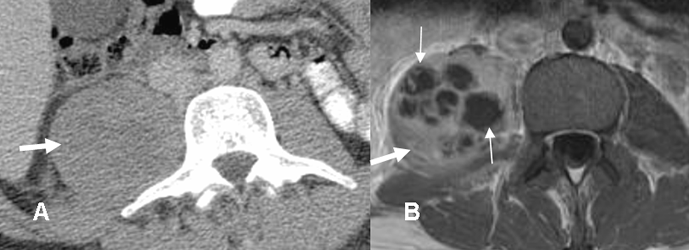

Fig 51. Osteomielitis TBC.

A: TAC axial y B: RM sagital en T1 con contraste. Igual paciente anterior. Engrosamiento en el músculo psoas derecho por absceso, como complicación de la osteomielitis. En la RM hay colecciones líquidas, que no realzan con el contraste. (Flechas delgadas).